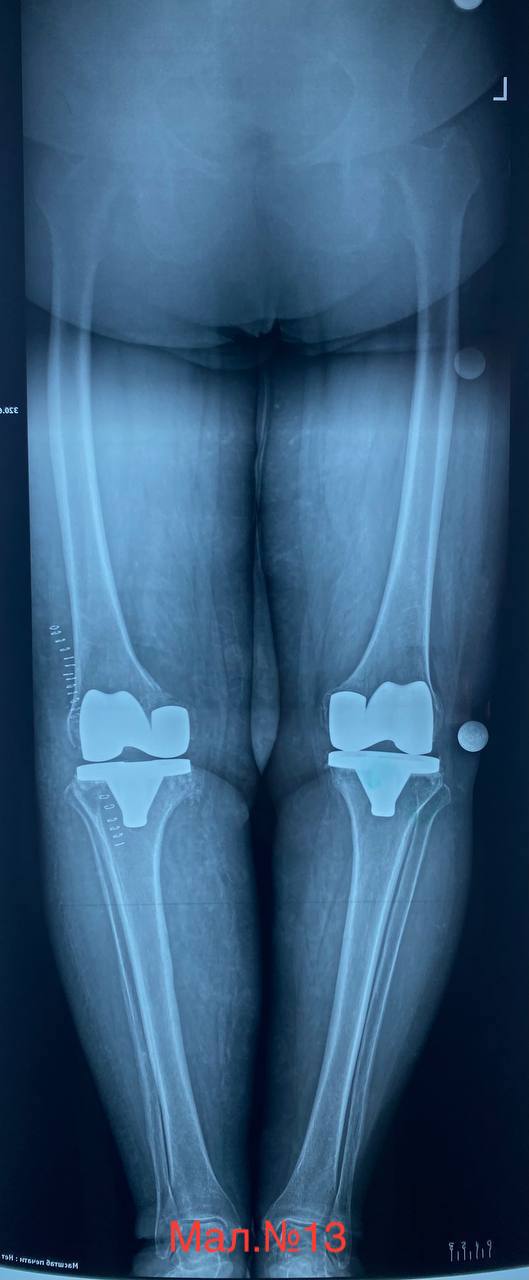

photo_2023-12-13 17.11.27